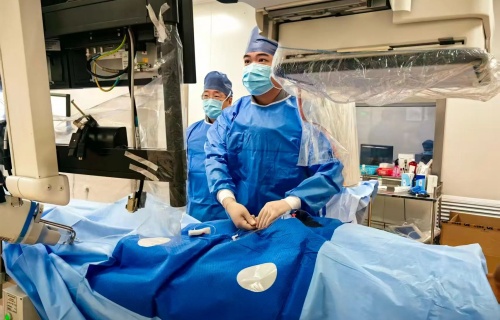

手术于9月4日进行。术中,肝胆外科副主任医师王福刚通过将内镜从患者创口进入直到十二指肠,在胆管开口处精确植入金属支架,将原来堵塞的“运输桥梁”再次支撑起来,使淤积的胆汁能够顺利通畅流出;麻醉科主任王志茹则全程在手术室密切检测患者生命体征变化。在手术团队的协助下,整个手术仅用时25分钟就顺利结束。